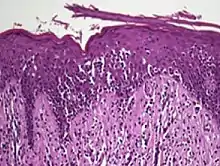

Diagnosis is sometimes difficult because the early phases of the disease often resemble inflammatory dermatoses (such as eczema, psoriasis, lichenoid dermatoses including lichen planus, vitiligo, and chronic cutaneous lupus erythematosus), as well as other cutaneous lymphomas.[10] Several biopsies are recommended, to be more certain of the diagnosis.

The criteria for the disease are established on the skin biopsy:[11]

- the superficial papillary dermis is infiltrated by a bandlike lymphocyte infiltrate

- epidermotropism

- presence of atypical T-cells with cerebriform nuclei in the dermal and epidermal infiltrates.

Pautrier's microabcesses are aggregates of four or more atypical lymphocytes arranged in the epidermis.[12] Pautrier microabcesses are characteristic of mycosis fungoides but are generally absent.

In the mycotic stage, infiltrative plaques appear and biopsy shows a polymorphous inflammatory infiltrate in the dermis that contains small numbers of frankly atypical lymphoid cells. These cells may line up individually along the epidermal basal layer. The latter finding if unaccompanied by spongiosis is highly suggestive of mycosis fungoides. In the tumorous stage a dense infiltrate of medium-sized lymphocytes with cerebriform nuclei expands the dermis.